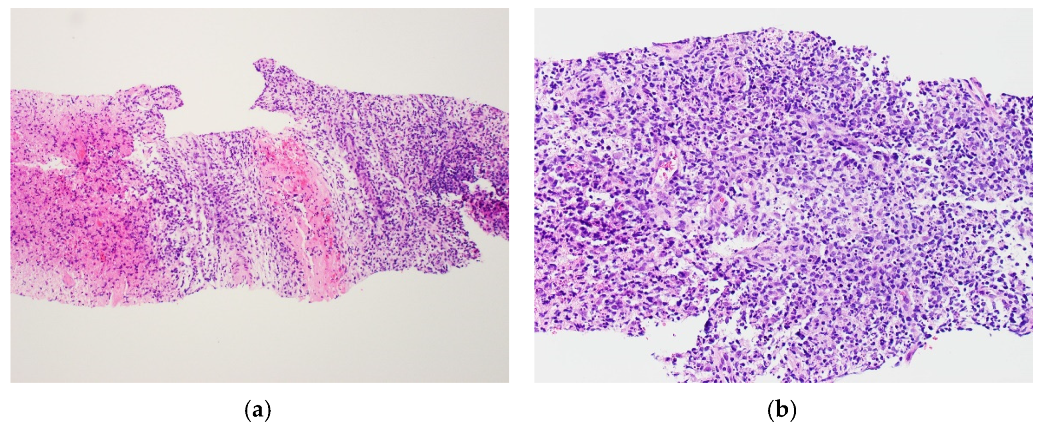

2. Case Report